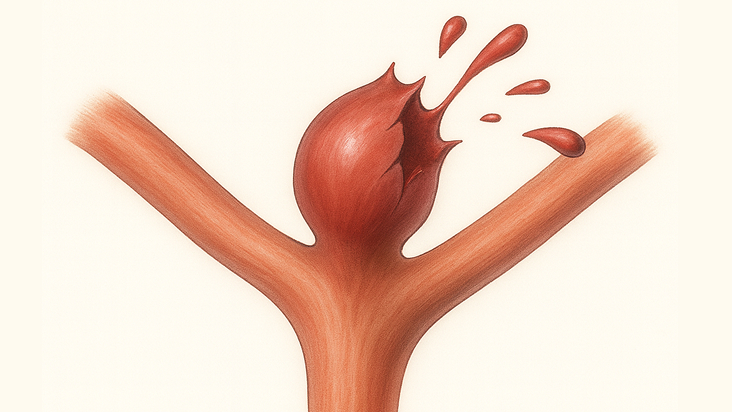

脳動脈瘤ができた血管

破裂して出血した状態

脳動脈瘤とは、脳の血管(動脈)の一部が風船のように膨らんで、こぶのようになった状態を指します。この「こぶ」が破裂すると、「クモ膜下出血」という命に関わる重篤な状態を引き起こします。

再び出血しないように、できる早く手術を行って止血処置を行うことが最も重要です。破裂脳動脈瘤にも、カテーテル治療(コイル塞栓術)や開頭手術(クリッピング術)が行われます。どちらの治療も「再出血を防ぐ」ことが目的です。

患者さんの状態や動脈瘤の場所によって最適な方法が選ばれます。一度クモ膜下出血を起こすと、3人に1人は亡くなり、3人に1人は後遺症が残ると言われています。また再び破裂すると非常に危険(致死率は約50-70%)なので、できるだけ早く再出血を防ぐ治療が必要です。